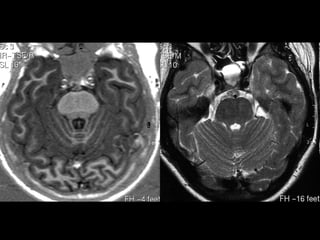

CENTRO SEMIOVAL/COROA RADIATA

MESENCÉFALO

COLÍCULOS

SUPERIORES

INFERIORES

• TETO MESENCEFÁLICO (LÂMINA QUADRIGEMINAL)

• PEDÚNCULOS CEREBELARES SUPERIORES E

• IV VENTRÍCULO

• CEREBELO - HEMISFÉRIOS